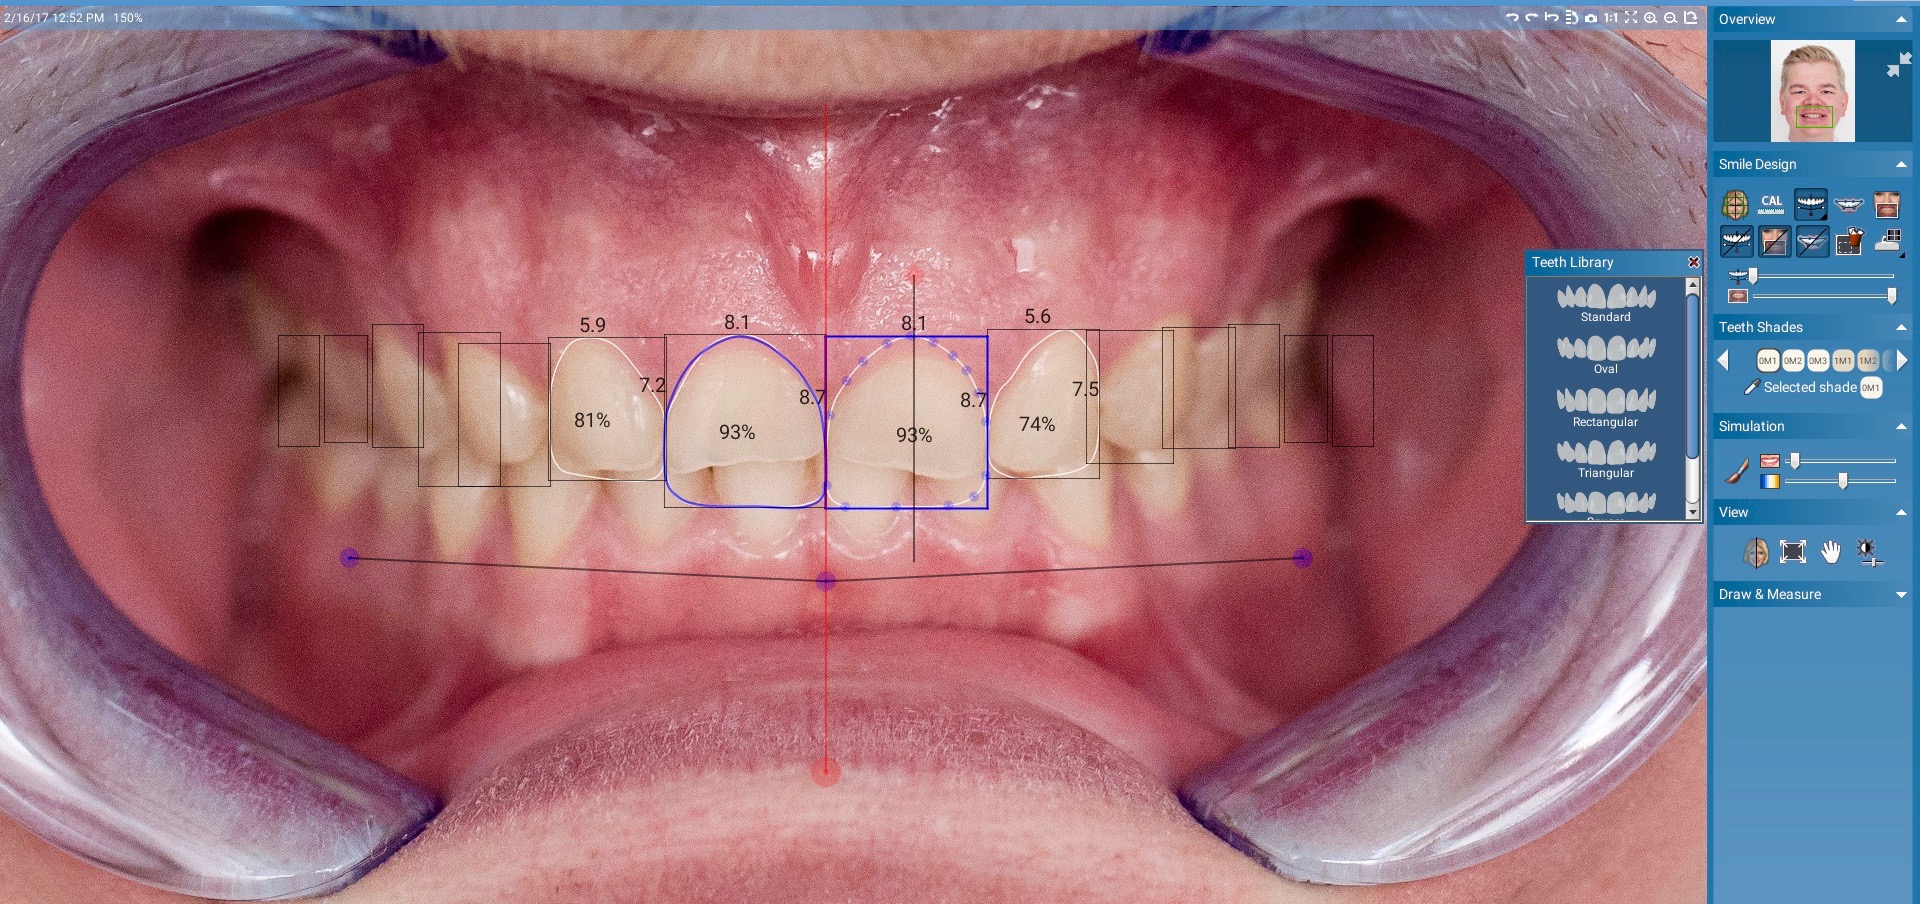

Digital technology is not only great for diagnosis and treatment planning, it also allows that plan to be easily integrated into the restorative workflow. This is a distinct advantage over conventional workflows, especially in esthetic cases when it is critical to meet patient expectations. An illustration of this is a patient presenting with a desire to address his chipped maxillary incisors to make them more esthetic (Figure 1). Using digital photography, a retracted photograph of the patient's teeth was imported into smile-design software, which provided a quick and simple means of establishing a symmetrical restorative design for the patient (Figure 2). Within the same software, the proposed restorations were then overlaid on a full-face smiling photograph (Figure 3), and the patient was able to compare before-and-after photographs (Figure 4). The patient approved of the proposal, which was then imported into CAD software to facilitate fabrication of the final restorations based on the smile-design proposal (Figure 5).

Fig 2. Planning of proposed restorations in smile-design software.

Figure 2